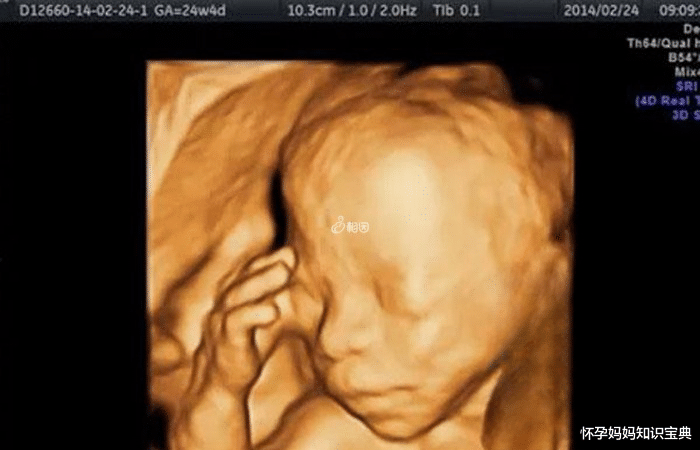

四维彩超是孕期排畸检查之一,能够观察到胎儿的面部、四肢以及主要器官的生长发育是否正常,一般是在怀孕22-24周左右进行检查。现在不少人认为通过四维彩超检查就能知道胎儿的性别,并且网上还流传着四维一看就是男孩的参照图,认为面部轮廓大、正面鼻大嘴大的就是男孩,对这个方法感兴趣的朋友可以详细了解一下。

四维彩超检查的主要目的是判断胎儿的面部以及神经系统是否存在异常,虽然能够清楚的看到宝宝的脸以及生殖器官,但是一般医生是不会拍下泄露胎儿性别的图片的。但是还是有不少好奇胎儿的性别的妈妈,会通过四维图片进行预测,下面就为大家介绍一下四维一看就是男孩的特征:

面部特征民间也有观察四维检查单图像的说法。如果宝宝的面部轮廓比较大,可能会怀男宝,如果面部轮廓比较小,可能会怀女宝。网传四维正面鼻大嘴大是男孩,孕妇可以通过宝宝的四维图片来进行观察,但也有一种情况表明宝宝的面部特征仅仅是遗传父母的面部特征而已,与性别无关,这就需要孕妇自行判断了。

胎儿下巴尖孕妇在完成四维彩色多普勒超声检查后,可以仔细观察检查表,其中有许多信息都是可以观察出一些小差别的。在四维彩色多普勒超声图像上,已经大致能够看出胎儿的脸部轮廓了,而网传胎儿的脸有尖尖的下巴,那么怀男孩的可能性很大,如果胎儿的下巴是圆的,那么怀女孩的可能性更大。

四维彩超是在三维彩超的基础上,更加清晰和直观的观察胎儿发育情况和肢体的活动情况、胎儿的性别等。四维彩超可以检测出胎儿发育是否正常以及是否患有发育问题等,通过四维彩超还能够观测出孕妇腹中的羊水情况以及是否有胎儿脐带绕颈等情况,四维彩超对于排除畸形是非常必要的。四维判断生男生女的方法在孕期,孕妇们比较关心的一件事情应该就是宝宝的性别了,但我国明令禁止非医学必要的胎儿性别鉴定,医生会主动回避胎儿性别特征,也可能将泄漏胎儿性别的部分进行处理。所以,宝妈们只能通过一些其他方法来进行判断,例如超声检查、四维彩超等等,其中四维彩超单子图解看男女的准确率还是比较高的,在80%左右。